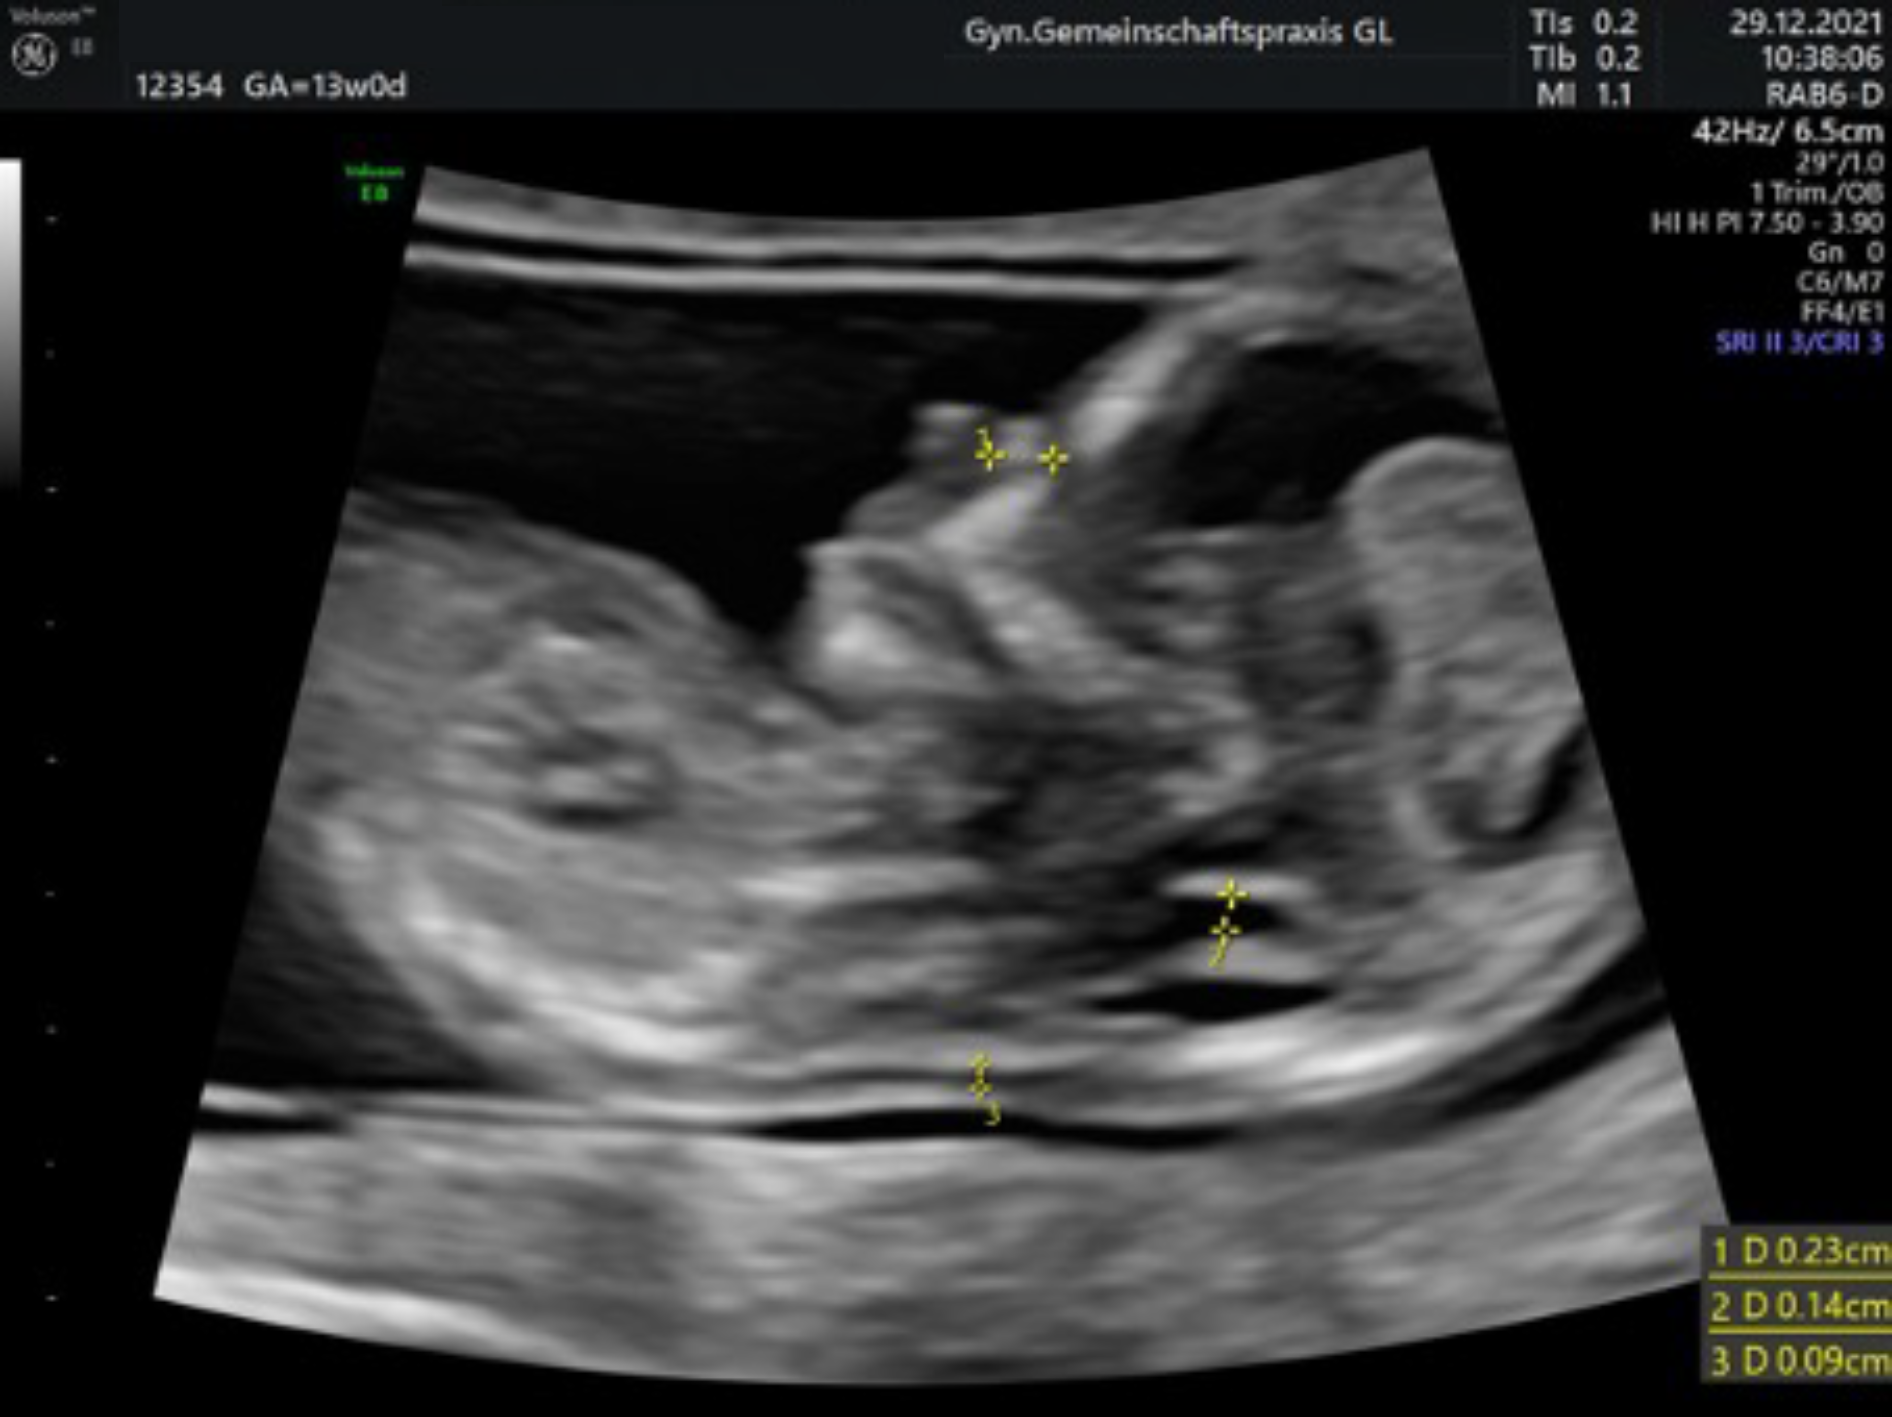

Ersttrimesterscreening mit individueller Risikoberechnung

(auch Nackentransparenzmessung/frühe Organdiagnostik genannt)

Zwischen der 12. und 14. Schwangerschaftswoche lagern die Kinder Flüssigkeit im Bereich des Nackens ein. Bei manchen Kindern ist dies verstärkt der Fall und kann dann zusammen mit Veränderungen bestimmter Blutwerte der Mutter einen Hinweis auf eine Chormosomenstörung (z. B. ein Down-Syndrom) geben.

In sehr großen Studien an über 100.000 Schwangerschaften wurden diese Messwerte mit der Risikoerhöhung für einen Chromosomenfehler des Kindes überprüft, die Vorhersagegenauigkeit ist deutlich besser, als die Abschätzung über das Alter der Mutter (bis ca 90%).

Zusammen mit einem ausführlichen Ultraschall (frühe Organdiagnostik) incl. des kindlichen Nasenbeins, der intakten Funktion einer Herzklappe und dem Blutfluss zwischen Mutter und Kind wird die Zuverlässigkeit der Risikoberechnung noch genauer und kann dann auch auf andere Fehlbildungen, z. B. einen Herzfehler oder einen offenen Rücken, hinweisen.